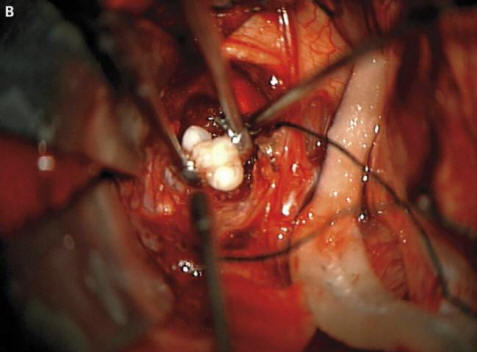

Hirurzi iz američke države Merilend morali su ga provesti najtežih operacija u njihovoj praksi. Roditelji četiri meseca dečki su oglasili uzbunu i posle otišli doktorima primijetili da im glava djeteta raste prebrzo. Ljekari obavili pregled i ustanovili da mu je zub porastao u mozgu pacijenta.

Fotografija iz otvorenih izvora Kako su uplašeni roditelji objasnili hirurzi i onkologa je to zbog formiranja rijetke urođene tumori – kraniofariniomi, piše New England Journal of Medicine. Ova neoplazma u velikoj većini slučajeva benigna, međutim, može narasti do veličine lopte golf i uzrokuje smanjenje osjećaja mirisa, oštećenje sluha i vida i povećava i intrakranijalni pritisak. Istraživači uvijek sumnja da su se ovi tumori koji se pojavljuju kod djeteta već ranije trudnoća, nastala iz istih ćelija kao i zubi, otkad su otkrili velika nakupljanja kalcijuma, ali pravi formirani zub prije ovog slučaja koji ne mogu pronaći računati.

Hirurzi su uspješno uklonili fotografiju iz otvorenih izvora Tumor, dečko, rekli su, ide dobro. Međutim zub koji odrastao mu je hipofiza, a opet je poremetio mozak, pravilna proizvodnja hormona – pacijent će ih morati ranije uzimati kraj života. Ovaj slučaj s pravom može zauzeti svoje mjesto popis najčudnijih operacija koje obavljaju onkolozi. U međuvremenu u mladić iz Irana, koji je morao liječite dlakave oči. Čudan mu se tumor u oku gotovo pojavio odmah po rođenju, međutim s dobi od 19 godina znatno se povećala u veličine (do 0,6 cm) i sprečavali zatvaranje kapka, osim toga, od njega ukočena kosa je počela rasti. Ljekari su mu uklonili tumor i to otkrili ovo je limbalni dermoid – izuzetno rijetko, obično benigne edukacije. Prema riječima ljekara u tom slučaju je ako je mladić nastavio da se povlači s lijekovima, njegova oteklina ne samo da može rasti kosu, već se i početi znojiti: s vremenom na neoplazmi se često pojavljuju odgovarajuće žlijezde.